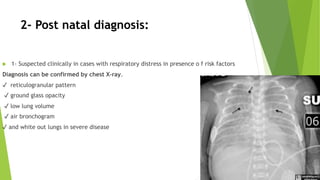

This document discusses respiratory distress and respiratory distress syndrome in neonates. It defines respiratory distress and describes the clinical signs. Various pulmonary and non-pulmonary causes are outlined. Respiratory distress syndrome, also known as hyaline membrane disease, is described in detail, including risk factors, pathophysiology, clinical presentation, investigations, complications, prevention, and treatment approaches like surfactant administration and nasal continuous positive airway pressure. The prognosis depends on gestational age and quality of care provided.